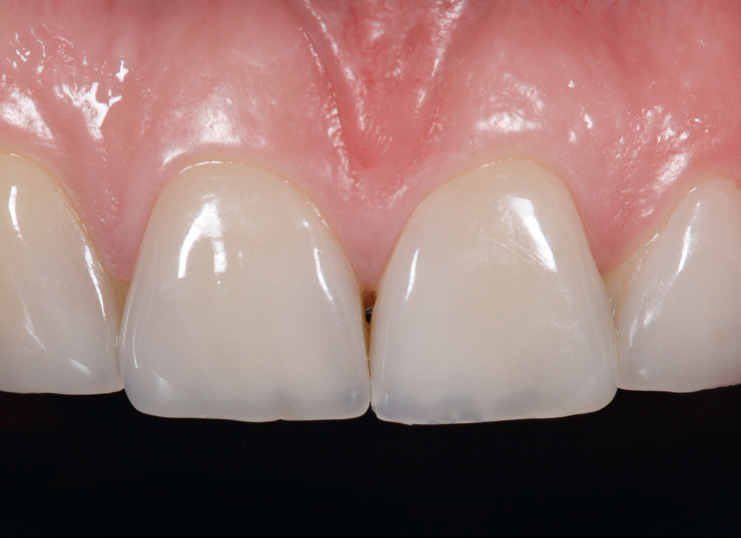

Initial situation. Veneers on teeth 11 and 21 repaired with 3M™ Filtek™ Ultimate Universal Restorative.

Both veneers in place after clean-up. Note the perfect marginal integration of the ceramic and enamel.